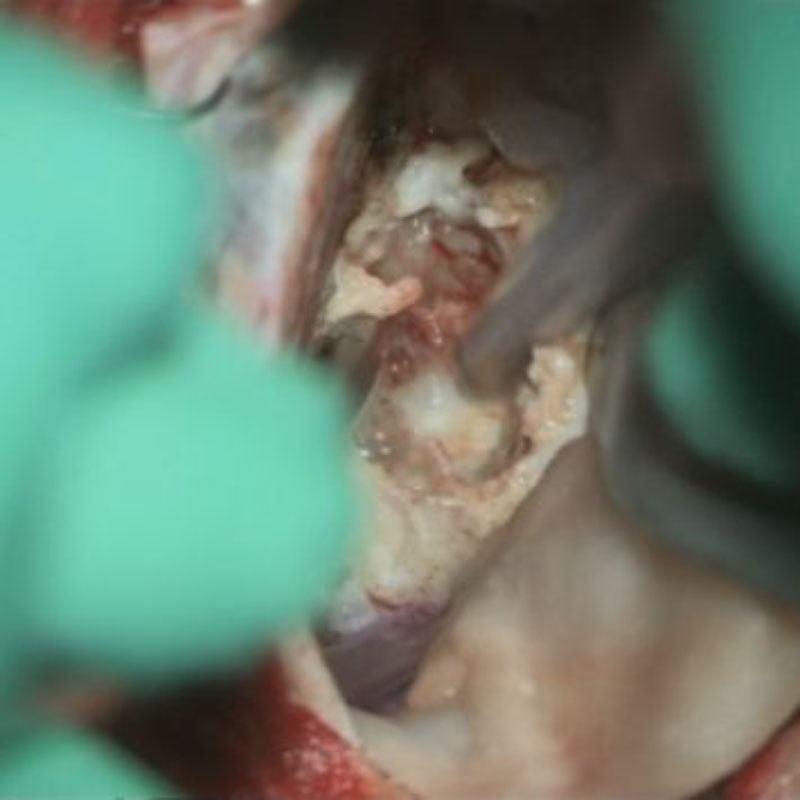

707

'25年12月

80代

髄膜腫

頭蓋内腫瘍摘出術

No.’25_109 摘出 前

No.’25_109  摘出 中

No.’25_109 摘出 後